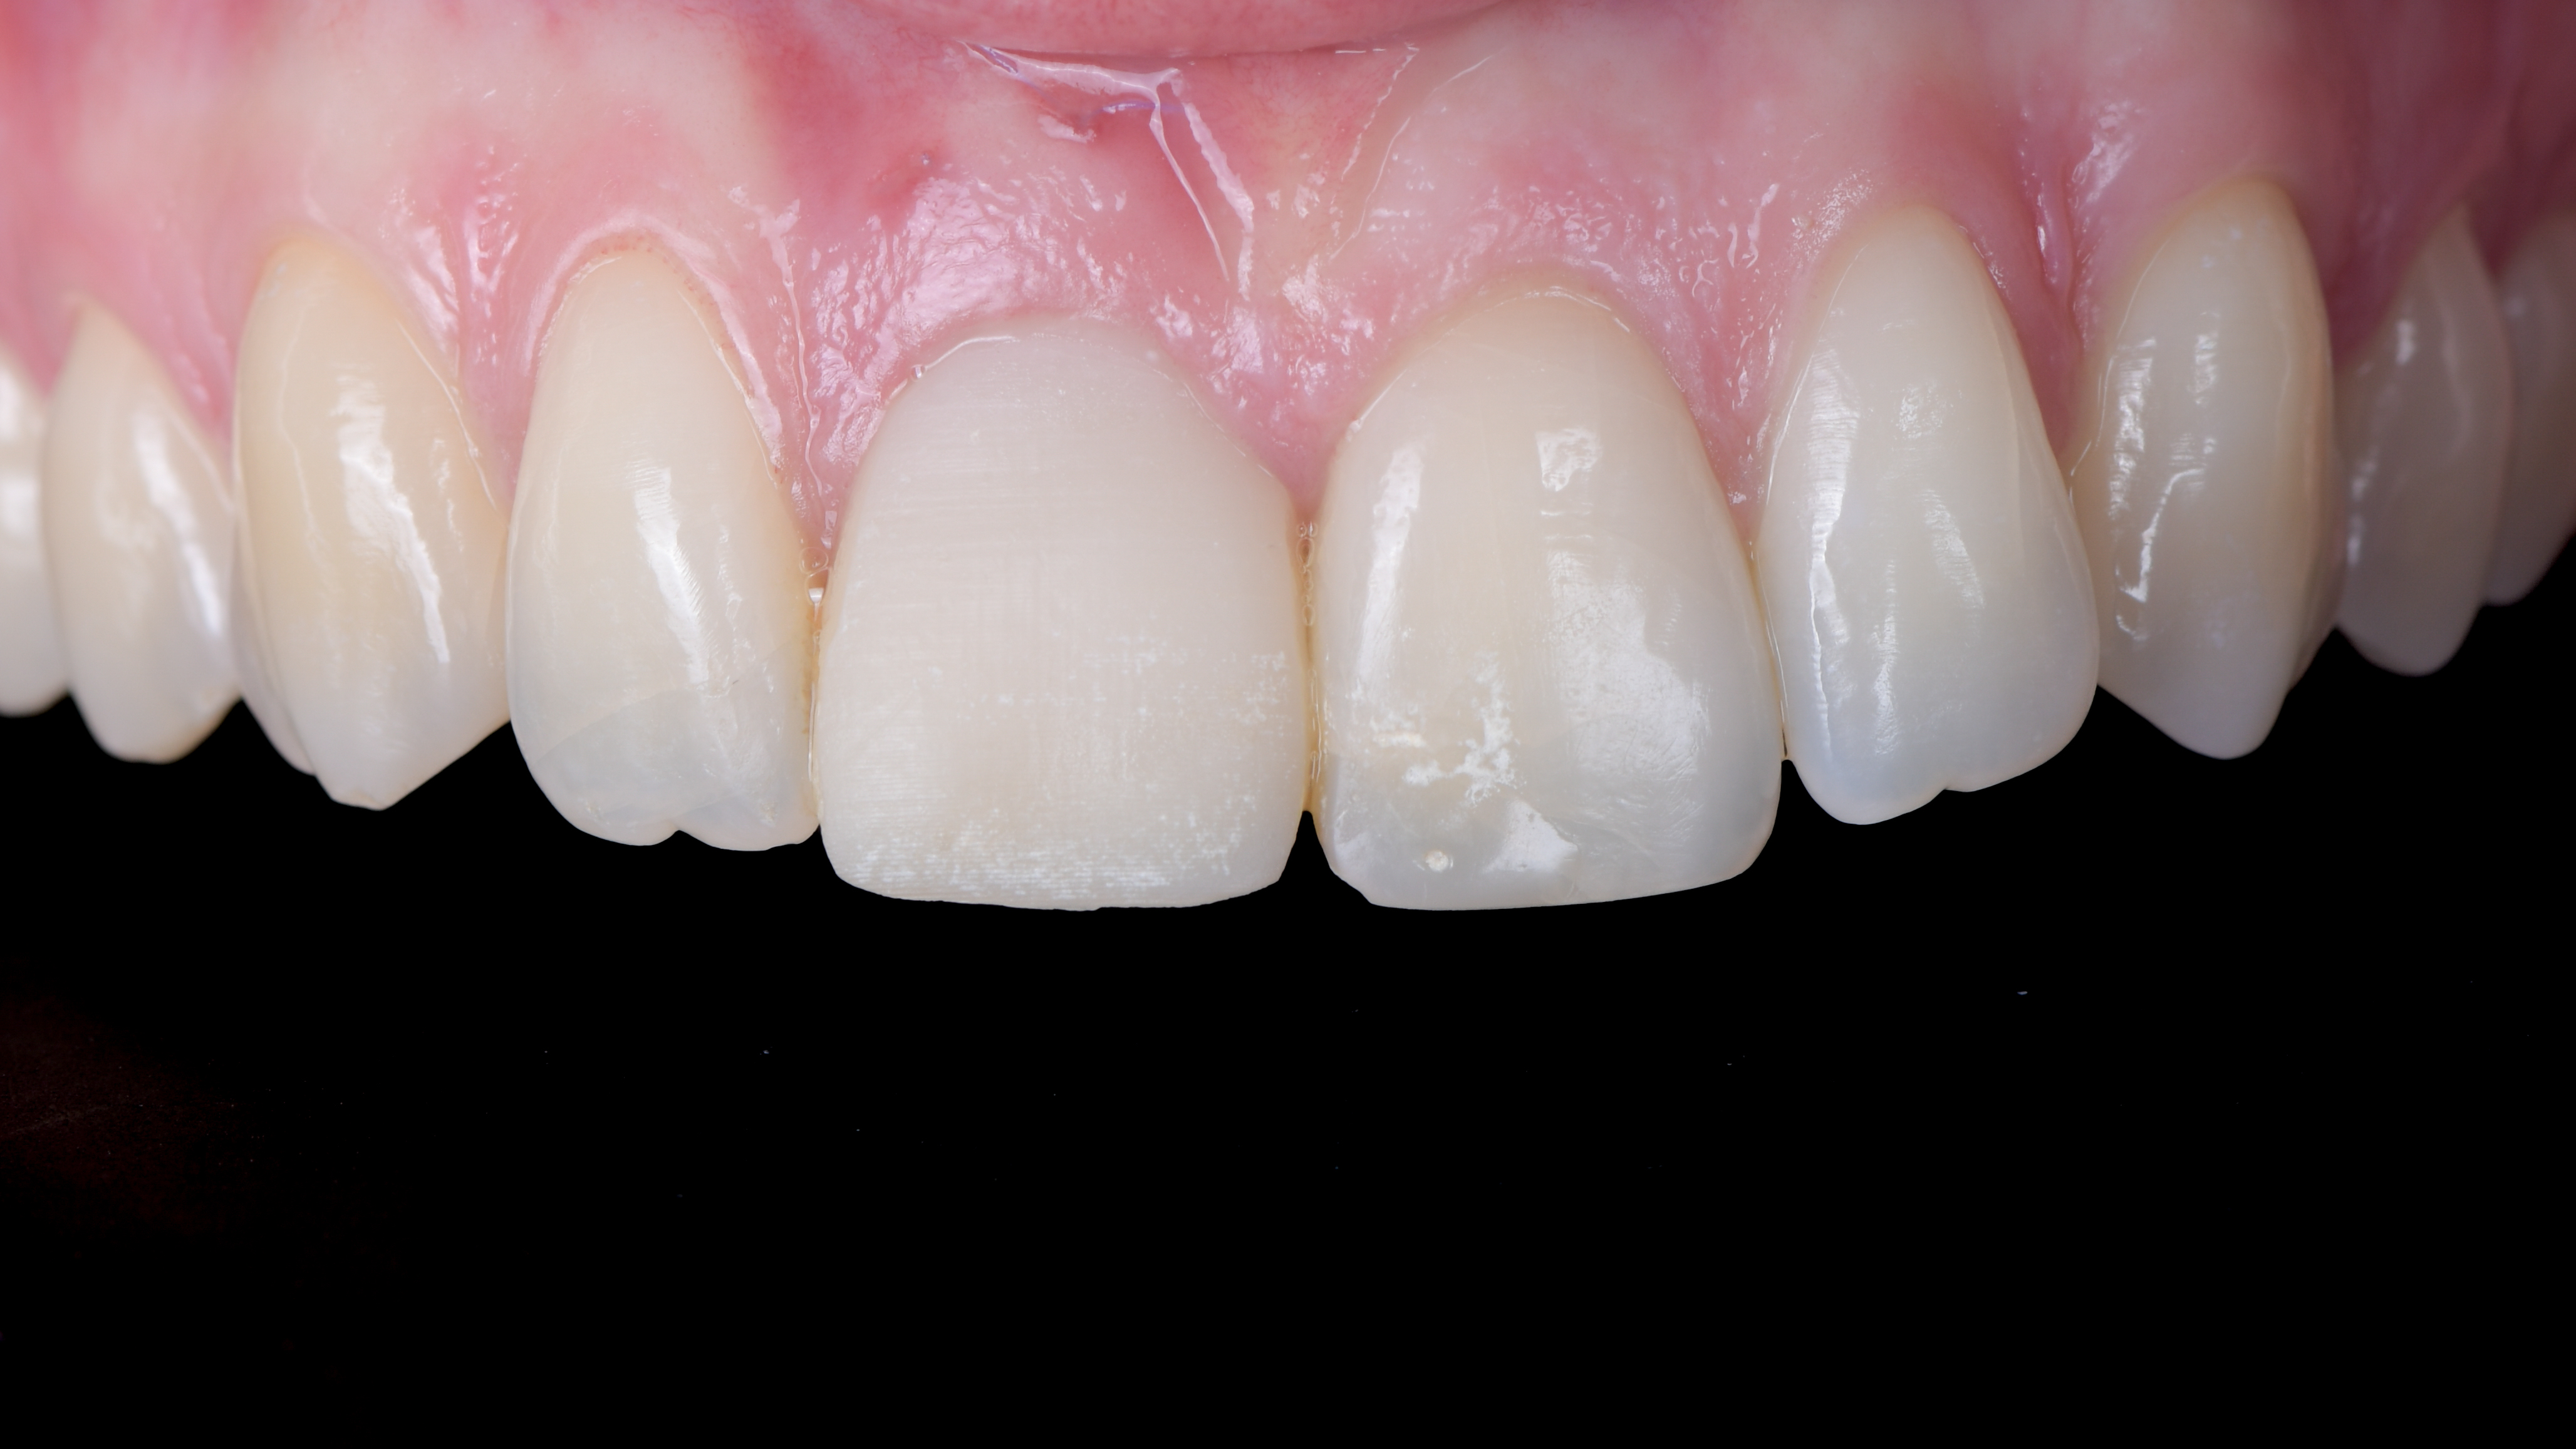

Après une période de cicatrisation de 3 mois, la patiente est revue pour réaliser la prothèse d’usage (Photo 18). Nous réalisons plusieurs empreintes numériques :

La patiente revient pour la pose de la prothèse d’usage. Nous réalisons donc un essayage de cette prothèse d’usage avant de réaliser le composite sur la dent 21.

Nous constatons que la cicatrisation est alors optimale et que la prothèse d’usage s’intègre parfaitement à son environnement (Photo 20).